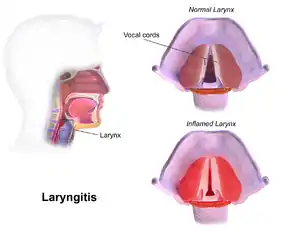

Visual diagnosis

The larynx itself will often show erythema (reddening) and edema (swelling). This can be seen with laryngoscopy or stroboscopy (method depends on the type of laryngitis).[7]: 108 Stroboscopy may be relatively normal or may reveal asymmetry, aperiodicity, and reduced mucosal wave patterns.[22]

Other features of the laryngeal tissues may include

- Redness of the laryngeal tissues (acute)

- Dilated blood vessels (acute)

- Thick, yet dry laryngal tissue (chronic)

- Stiff vocal folds

- Sticky secretions between the vocal folds and nearby structures (the interarytenoid region)